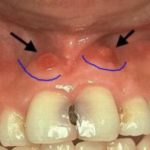

Первое, что чаще всего замечает пациент – небольшой мешочек на мягких тканях во рту, немного напоминающий прыщ. При этом десна отекает, краснеет, а в пораженной области наблюдается пульсирующая боль, свидетельствующая об образовании очага с гноем. Болевые ощущения усиливаются при надавливании на место рядом с образованием. Зубы, рядом с которыми появилась фистула, могут стать более подвижными. Еще один тревожный симптом – неприятный запах изо рта. Несмотря на довольно явные признаки, глядя на них, можно перепутать свищ с другими недугами: